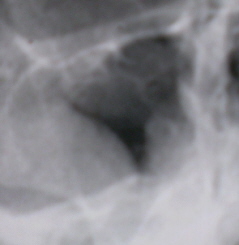

В этих случаях снимок, произведенный в вертикальном поло­жении, обычно вносит ясность. На рентгенограмме выявляется горизонтальный уровень жидкости или параболическая верхняя ее гра­ница, отличающаяся от острого синуита тем, что она гораздо короче, не доходит до костной наружной стенки пазухи.

Иллюстрация 10. На увеличенном цифровом изображении гайморовых полостей, с применением режима «эквилизация» - негативный вариант слева определяется почти тотальное снижение прозрачности гайморовой полости за счет кистозного образования. Справа в гайморовой полости определяется менискообразный уровень жидкости, «не доходящий» до латеральной стенка гайморовой полости. По верхнему и медиальному контурам правой гайморовой полости определяется пристеночное снижение прозрачности, неоднородной ширины, с не ровным, не чётким контуром.

Такое расположение жидкости косвенно подтверждает занятость прилегающего к костной стенке участка пазухи пристеночными наслоениями на почве гиперплас­тического процесса.